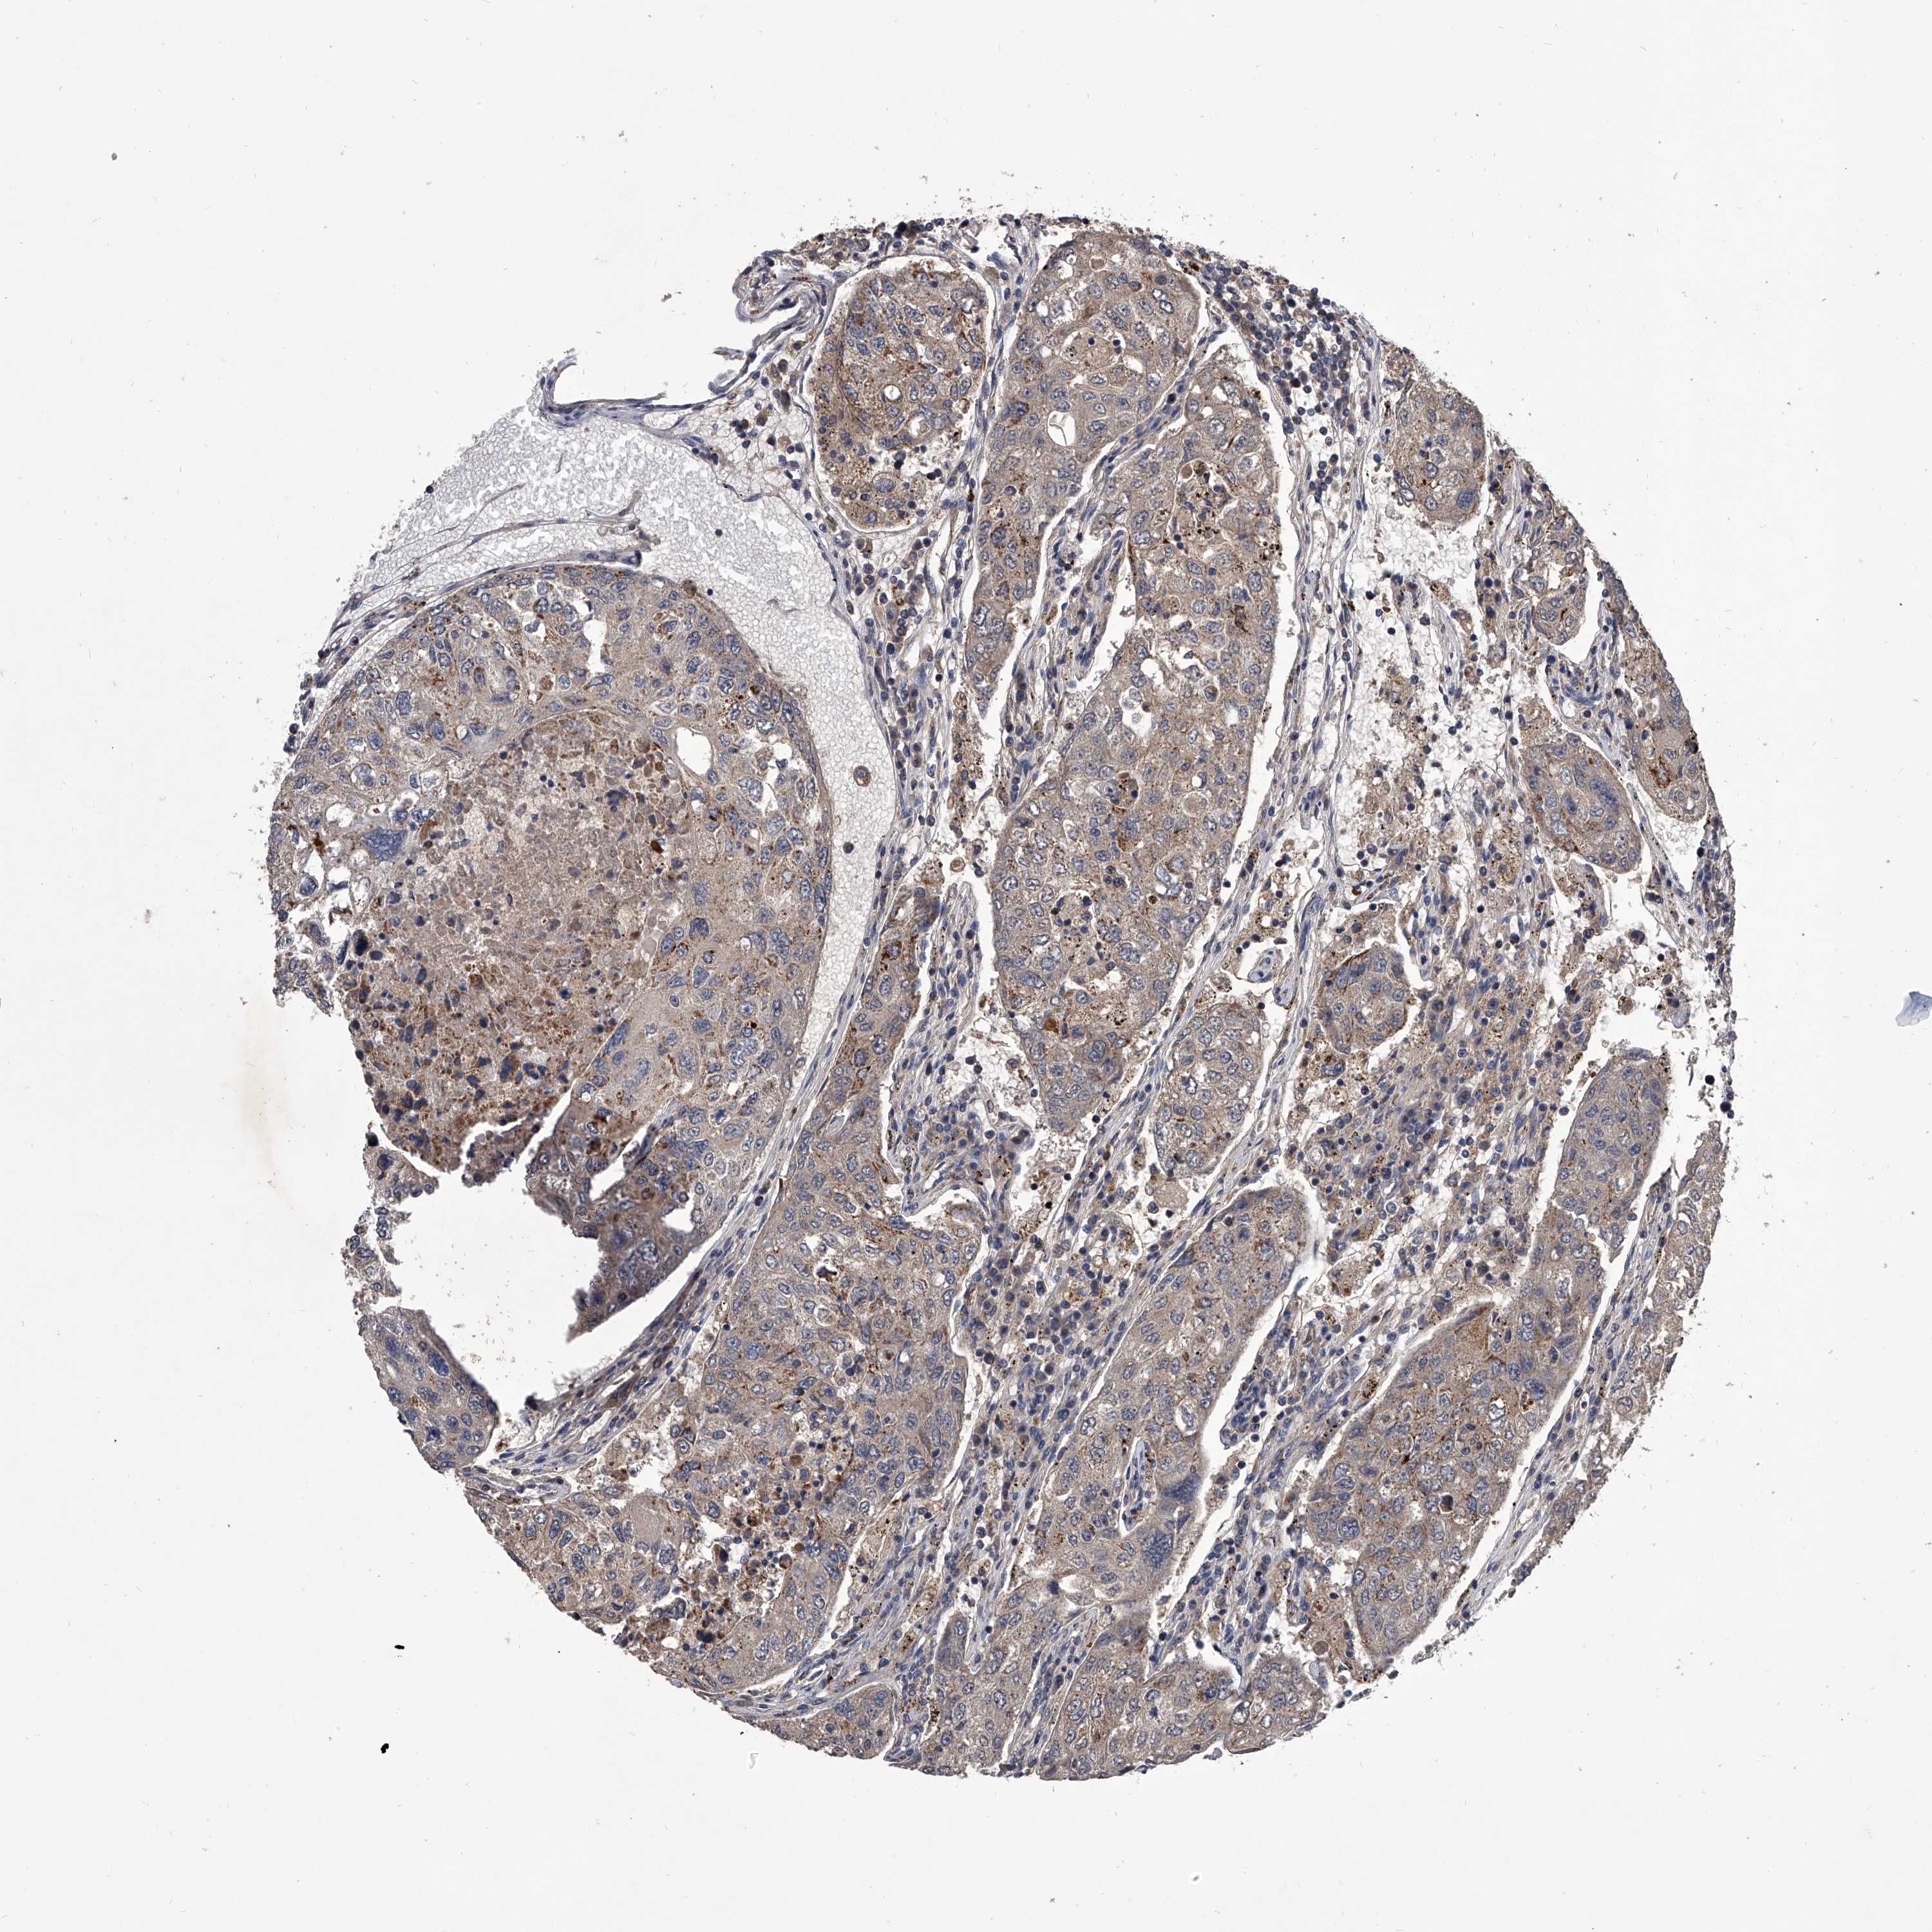

UROTHELIAL CANCER - Protein expressioni

A mouse-over function shows sample information and annotation data. Click on an image to view it in a full screen mode. Samples can be filtered based on level of antibody staining by selecting one or several of the following categories: high, medium, low and not detected. The assay and annotation is described here.

Antibody stainingi

Antibody staining in the annotated cell types in the current human tissue is reported as not detected, low, medium, or high, based on conventional immunohistochemistry profiling in selected tissues. This score is based on the combination of the staining intensity and fraction of stained cells.

Each image is clickable and will lead to virtual microscopy that enables deeper exploration of all samples and also displays staining intensity scores, fraction scores and subcellular localization as well as patient and tissue information for each sample.

Antibody HPA030278

Antibody CAB004511

Urothelial carcinoma, Low grade

Urothelial carcinoma, High grade